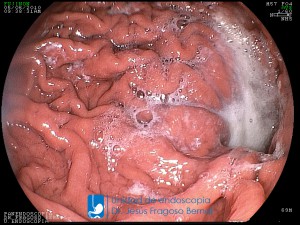

La Unidad de Endoscopía fue creada en 2002 por el Dr. Jesús Fragoso Bernal, es pionera en el estado por la utilización de la tecnología más avanzada, que nos permite ofrecer servicios integrales de diagnóstico y tratamiento para las enfermedades del aparato digestivo.

El profesionalismo de nuestro personal, altamente especializado, se distingue por la calidad y calidez de nuestros servicios con el objetivo de brindar una atención de excelencia en el ambiente más confortable para comodidad y seguridad de nuestros pacientes.

"La Unidad de Endoscopía se ha caracterizado por un progreso continuo desde su inicio marcando la pauta en los procedimientos endoscópicos en el estado de Tlaxcala y estando siempre a la vanguardia tecnológica."

Dr. Jesús Fragoso Bernal